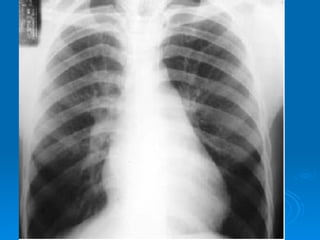

Radiographie thoracique Silhouette cardiaque Débord de  l’arc inférieur droit  ,dilatation de OG avec  aspect en   double contour Saillit de  l’arc moyen gauche  avec aspect en  double bosse  traduisant la dilatation du tronc de l’artére pulmonaire et l’auricule gauche Poumon mitral Redistribution vasculaire vers les sommets Oedème interstitiel Opacités réticulo nodulaires peri hilaire Lignes de Kerley Epenchement pleural

Radiographie thoracique Silhouettecardiaque Débord de l’arc inférieur droit ,dilatation de OG avec aspect en double contour Saillit de l’arc moyen gauche avec aspect en double bosse traduisant la dilatation du tronc de l’artére pulmonaire et l’auricule gauche Poumon mitral Redistribution vasculaire vers les sommets Oedème interstitiel Opacités réticulo nodulaires peri hilaire Lignes de Kerley Epenchement pleural